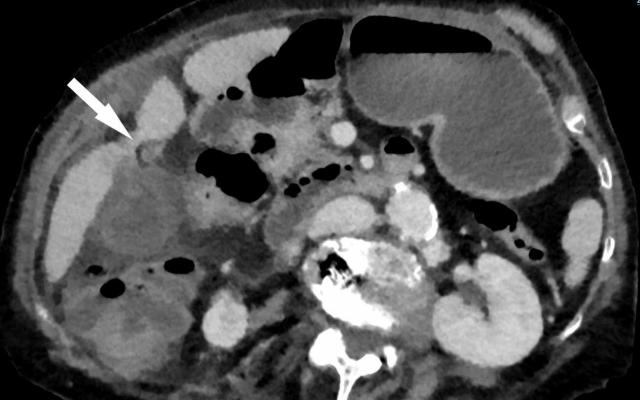

Wij beschrijven een 59-jarige man met een eerder behandeld melanoom op de behaarde hoofdhuid. Hij meldde zich met recidiverende buikpijn en anamnestisch melena. Vanwege het vermoeden van cholecystitis onderging hij met spoed een cholecystectomie. Nadien werd een galblaasmetastase van het melanoom vastgesteld.

Gastro-intestinale metastasen van een melanoom blijven vaak asymptomatisch en worden daardoor pas ontdekt bij complicaties, zoals obstructie, bloeding of perforatie. Bij patiënten met een melanoom in de voorgeschiedenis en nieuwe abdominale klachten of ijzergebreksanemie moet aan abdominale metastasering van het melanoom worden gedacht. Omdat intra-abdominale metastasen vaak multifocaal zijn, zijn beeldvormend en pathologisch onderzoek essentieel. De behandeling is primair systemisch en multidisciplinair, met eventueel aanvullende chirurgische verwijdering van symptomatische metastasen.